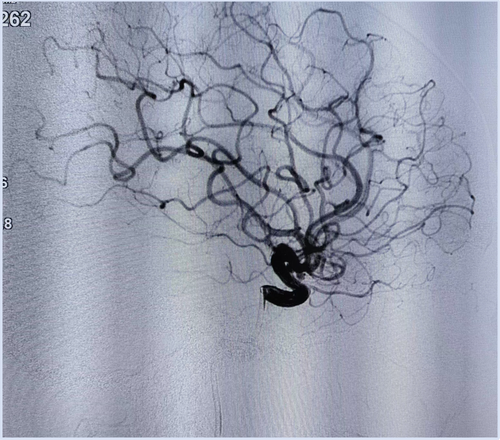

首例破冰——奉节县中医院:顺利开展首例未破裂颅内动脉瘤介入栓塞术

近日,奉节县中医院脑外科成功开展首例未破裂颅内动脉瘤介入栓塞术。该手术的成功开展,标志着医院神经介入工作取得新突破,迈上新的台阶。

据了解,患者周女士,50余岁,院外头颅CTA检查发现前交通动脉瘤及左侧颈内动脉C6段动脉瘤。患者及家属慕名而来到奉节县中医院脑外科,主管医生杨平在详细评估病情后,行未破裂颅内动脉瘤介入栓塞术。此手术耗时仅仅不到1小时,术后经科室精心护理,周女士康复出院,并送来锦旗致谢。通讯员:毛海